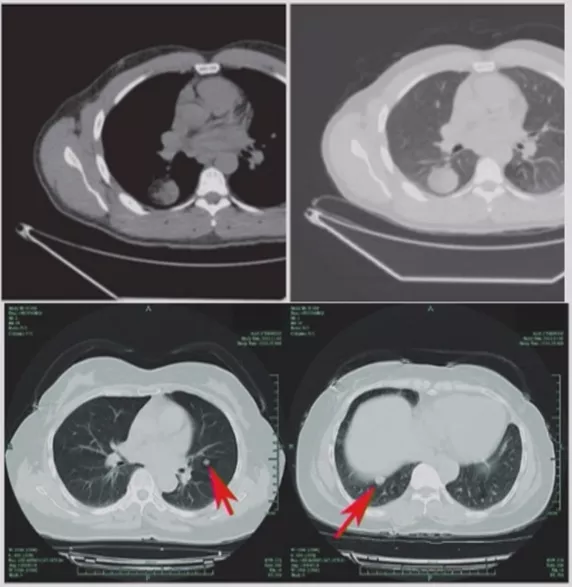

CT随访

1)病灶大小无变化、实性成分增多

这个结节大小没有太大变化,实性成分增多,这不是一个好征象,可以考虑手术。

2)病灶缩小、出现实性成分

容易被大家忽略的是结节的大小变小,但实性成分增多,值得大家重视。不要认为结节变小了就一定是良性。